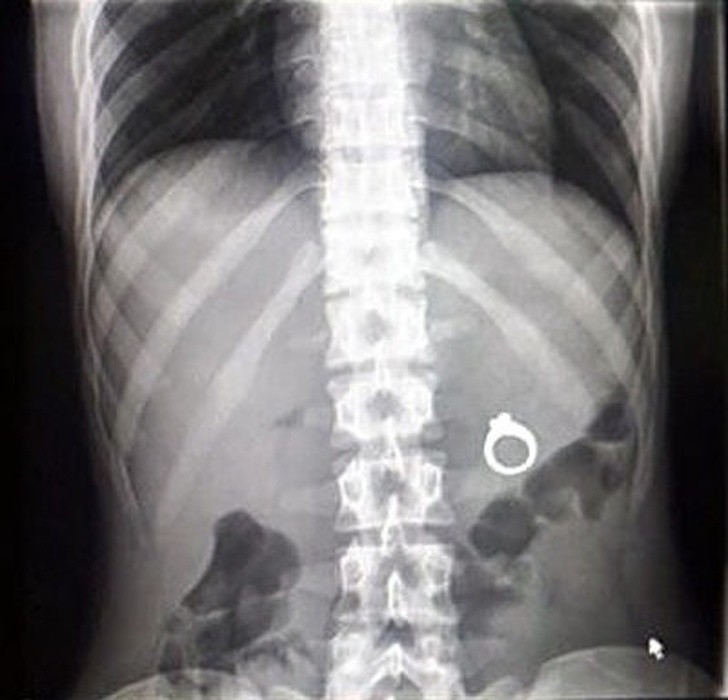

Ljudje smo resnično čudna bitja in se nam lahko zgodijo neverjetno bizarne stvari. Ti rentgenski posnetki bodo šokirali tudi tiste, ki mislijo, da so videli že vse.

Rentgen je eden najboljših izumov človeštva in v nekaterih situacijah je nepogrešljiv. Še posebej zato, ker se velikokrat zgodi, da ljudje, še posebno otroci, požirajo predmete, ki niso del dnevne prehrane. Da ne omenjamo psov, ki poskušajo prežvečiti vse, kar vidijo, in tako velikokrat pogoltnejo neprimerne stvari.

Radiologi so tako že precej navajeni, da na rentgenskih posnetkih vidijo čudne stvari in nekatere izmed teh, ki smo jih za vas zbrali v galeriji, jih sploh niso presenetile. Tukaj je 15+ odštekanih in na trenutke šokantnih rentgenskih posnetkov.